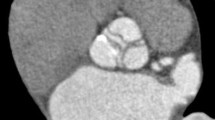

The different thresholds demonstrated various configurations of artifacts (Fig. 2). Specific testing between pairs of static valves indicated differences between all valves for the 2,000, 800 and 200 HU thresholds (Table 1, p < 0.001). For the −50 HU threshold no difference was found between the ON-X and CM valves (p = 0.43) but all other differences were significant (p < 0.001). The differentiation of the volume attributable to radiopaque components of the valve such as the ring and the leaflets from the total 200 HU threshold volume is demonstrated in Fig. 3. Specific testing between specific components demonstrated significant differences between ring volumes: 480 ± 3, 745 ± 12, 611 ± 12 and 147 ± 3 mm3 for the SJM, MH, CM and ON-X valve respectively (all differences p < 0.001). The leaflet volumes were 975 ± 11, 1,111 ± 25, 1,101 ± 15, and 1,336 ± 8 mm3 for the SJM, MH, CM and ON-X valve respectively. No difference existed between the CM and MH valve (p = 0.33), but the SJM and the ON-X had respectively a smaller and a larger leaflet volume than the other valves (p < 0.001). The artifact volumes (without leaflet and ring components) were 3,546 ± 141 mm3 for the SJM, 2,387 ± 103 mm3 for the MH, 2,003 ± 102 mm3 for the CM, and 3,033 ± 31 mm3 for the ON-X valve (all differences p < 0.001).

A Sagittal view of a St Jude valve prosthesis on multiplanar reformatting (a). The valve is placed in the mounting ring of the valve chamber which is inserted in the thoracic phantom at a 45° angle to the CT gantry. Volume rendered images of the same valve with the −50 (b) and 200 (c) threshold. The 800 threshold (d) includes prosthetic ring and leaflets and the 2,000 threshold (e) includes only the prosthetic ring

For pulsatile valves, leaflet motion was present during the 10% and 20% ECG intervals (leaflet opening motion in 100% and 49% of the valves respectively) and during the 60% and 70% ECG intervals (closing motion in 86% and 49% of the valves respectively). Leaflets were completely opened in all valves at 30–50% of the ECG interval and completely closed during 80–90 and 0% of the ECG interval (see Fig. 4).

Volume rendered images of hypodense artifact distribution patterns for the tilting disc Medtronic Hall valve (a) and the bileaflet ON-X valve (b). In each series, the upper panel represents a frontal view and the lower panel represents a side view of the artifact volumes identified with the −50 HU threshold. Leaflet motion is present in the following ECG intervals: at 10 and 20% (opening) and at 60 and 70% (closing). At 30–50% the valve is opened and from 80 to 90 and 0% the valve is closed

Analysis of pulsatile valves demonstrated a strong effect of the interval on hypodense (F = 41.5, p < 0.001) and hyperdense artifacts (F = 53.7, p < 0.001). The interpolation lines in the graphical depictions of the pulsatile artifacts (Fig. 5) follow a similar and mostly parallel pattern. There was no relevant interaction with valve type (F = 6.3 and 7.0, for hypo- and hyperdense artifacts respectively).

Four ECG intervals were identified which corresponded to the 4 phases of leaflet motion: 0% closed, 10% opening, 40% opened, 60% closing. Comparison of the 4 intervals for hypo- and hyperdense artifacts yielded the least artifacts for closed leaflets (both p < 0.001) followed by opened (p = 0.046 and p < 0.001 for hypo- and hyperdense artifacts respectively). The largest artifact volumes were found for either opening or closing leaflets (p < 0.001 for both artifact types, no difference between opening and closing). Post hoc analysis revealed higher increase of both types of artifacts for the MH valve compared to the other valves.